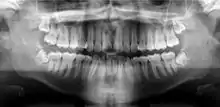

أشعة بانوراما

صورة الأشعة البانورامية أو التَّصْويرُ الشُّعاعِيُّ البانُورامِيّ (بالإنجليزية: panoramic radiograph) هي أشعة سينية بانورامية لفحص الأسنان للفكين العلوي والسفلي. تكون الصورة ثنائية الأبعاد لنصف دائرة من الأذن إلى الأذن. التصوير الشعاعي البانورامي هو شكل من أشكال التصوير المقطعي للمستوى البؤري. وهكذا يتم التقاط صور من عدة مستويات لعمل الصورة البانورامية المركبة، حيث يكون الفك العلوي والفك السفلي في النطاق البؤري والأجسام السطحية والأعمق من النطاق غير واضحة.